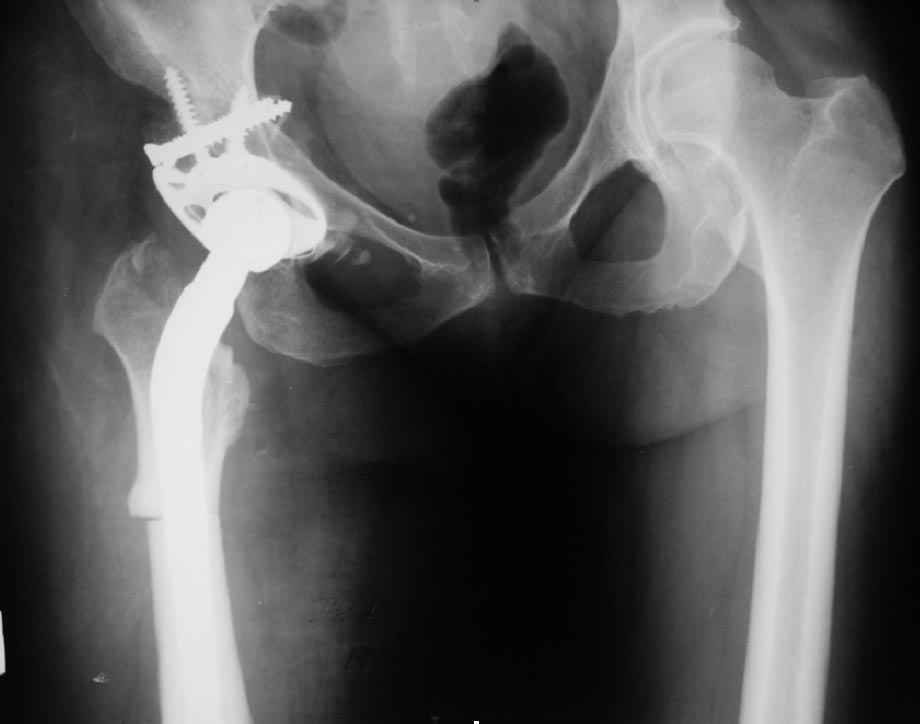

В прищепке случай 1999 года - эндопротезирование после операции Шанца-Илизарова. Возраст пациентки 45. Коррекция была в 17 лет. А Рыков Хабаровск.